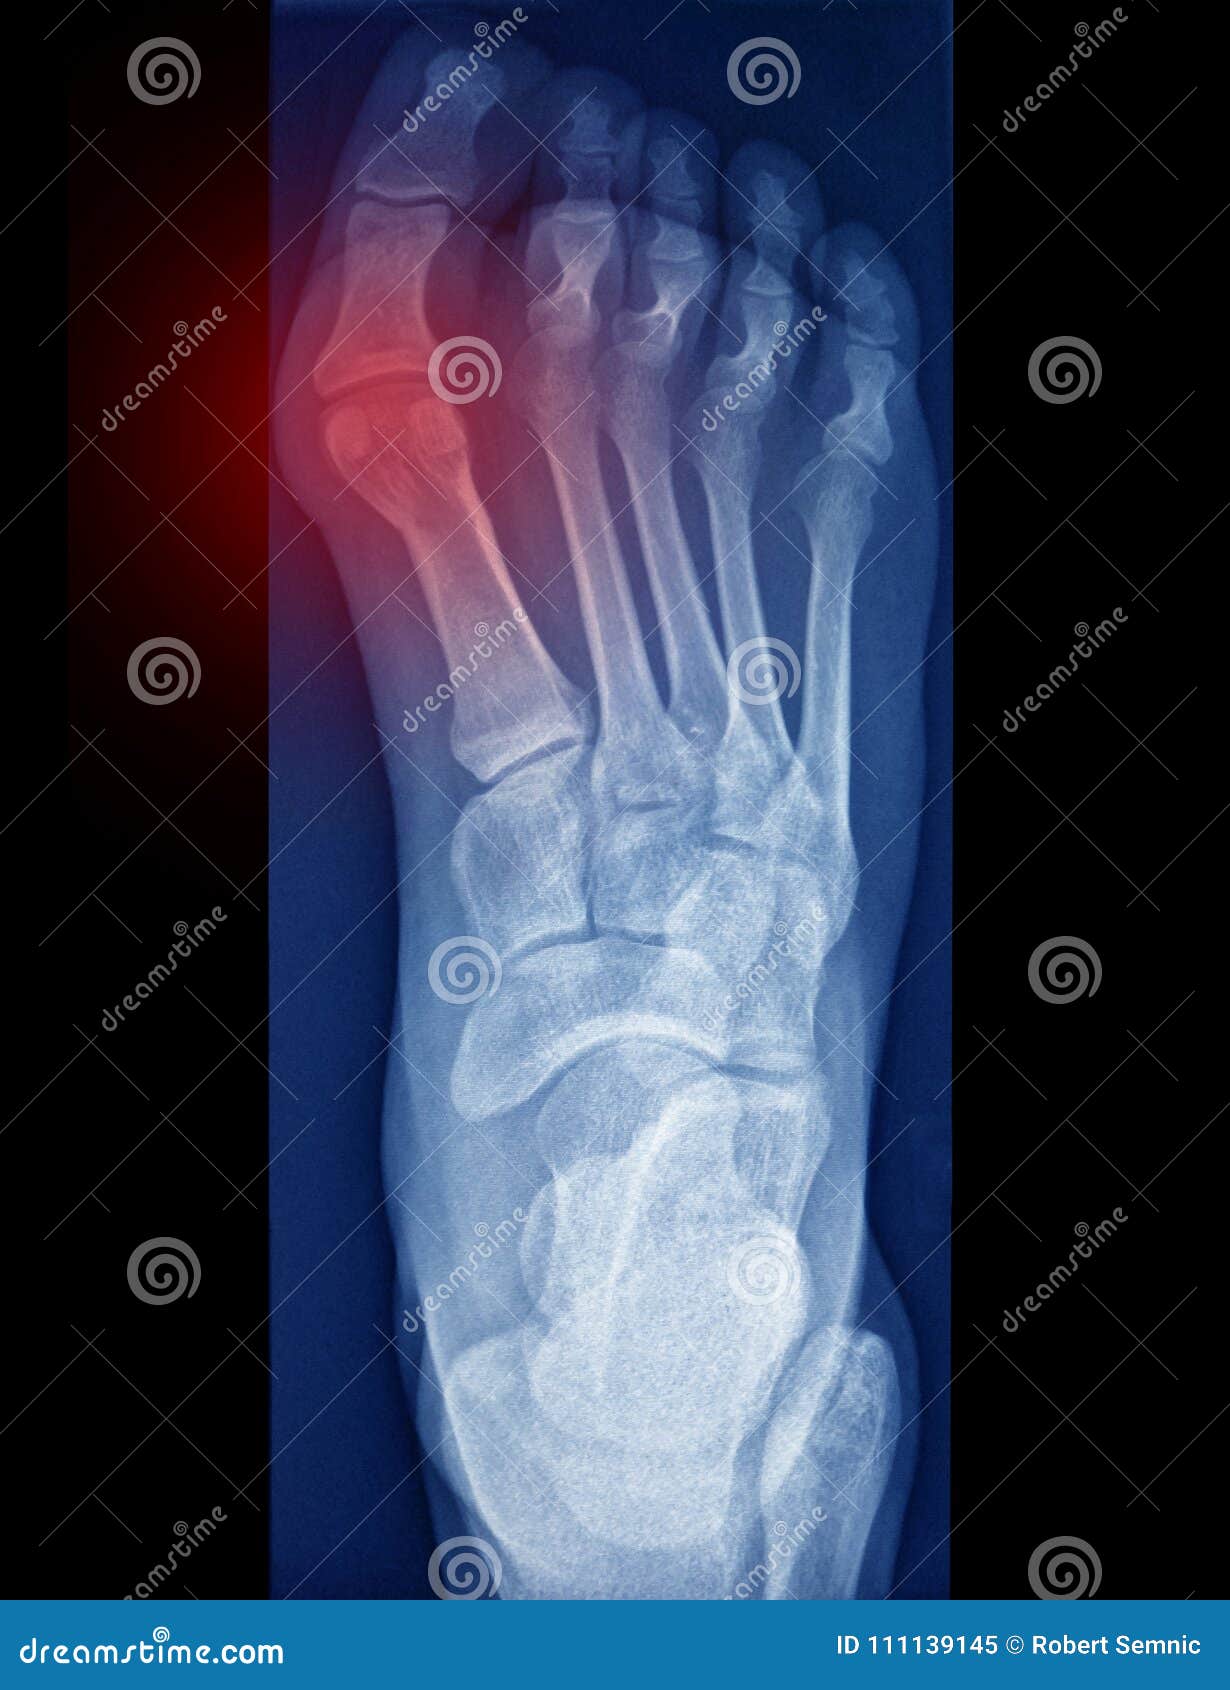

From www.dreamstime.com

Toe pain, x ray stock image. Image of adult, pain, healthy 111139145 Foot Pain Xray Bony tenderness at the navicular. Most arthritides are best evaluated with plain radiography. All common forms of arthritides affect the feet and can cause chronic foot pain. If pain is severe enough or if there has been an injury, your doctor. It typically presents in active. Bony tenderness at the base of the 5th metatarsal. Calcaneal apophysitis, also known as. Foot Pain Xray.